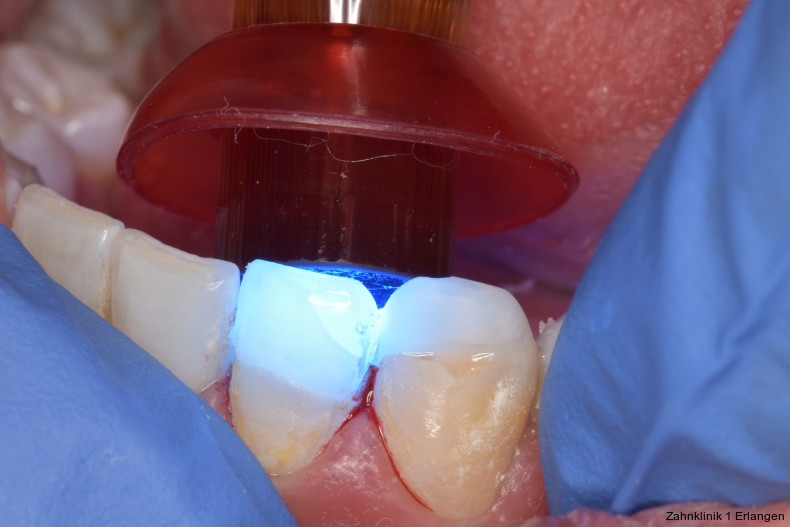

Bei Pulpaexposition ist die oberste Prämisse der Erhalt der Vitalität des Zahnes. Vor allem bei jungen Patienten und bei nicht abgeschlossenem Wurzelwachstum, aber auch bei erwachsenen Patienten ist die Vitalerhaltung die Methode der Wahl. Dabei spielen die Dauer und die Größe der Exposition keine wesentliche Rolle.10 Die oberste Gewebeschicht sollte zunächst im Sinne einer Mikropulpotomie angefrischt werden, was mit einem Diamantschleifer unter Wasserkühlung durchgeführt werden kann. Nach Blutstillung, zu der Natriumhypochlorit tropfenweise appliziert werden kann, wird das Sistieren der Blutung kontrolliert. Ist dies verifiziert, wird ein biokompatibles Material in direktem Kontakt mit dem Gewebe aufgebracht und der Zahn anschließend adhäsiv verschlossen.10 Dauert die Blutung an, beispielsweise weil der Unfall bereits mehr als 24 Stunden zurückliegt, kann tiefer pulpotomiert werden. Da eine traumatisch geschädigte Pulpa in der Regel vor dem Unfall gesund war, ist die Heilungskapazität meist sehr gut.11 Auch bei bestehender Exposition zur Mundhöhle hin über einen Zeitraum von Tagen kann die Pulpotomie noch hohe Erfolgsraten erzielen.

Tierexperimentelle Studien konnten zeigen, dass selbst bei über mehrere Tage hinweg freiliegender Pulpa Bakterien aus der Mundhöhle nicht tiefer als 2 mm in das Gewebe eindringen konnten.12 Kritisch ist dabei die erfolgreiche Blutstillung, die nach ca. fünf Minuten erreicht sein sollte. Die Erfolgsquoten der Pulpotomie nach Zahntrauma liegen deutlich über denen der direkten Überkappung bei über 90 Prozent. Dies ist auch in der revidierten Fassung der S2k-Leitlinie zum dentalen Trauma bleibender Zähne herausgestellt.3 Es ist zu beachten, dass bei begleitender Dislokationsverletzung die Durchblutung der Pulpa eingeschränkt oder sogar komplett unterbunden sein kann, was das Risiko des Misserfolges vitalerhaltender Maßnahmen signifikant erhöht.13 Daher sollte in solchen Fällen die Pulpektomie durchgeführt werden. Dies gilt ebenso bei umfangreichem Hartsubstanzverlust, wenn die definitive Restauration zusätzlich intrakanalär verankert werden muss.